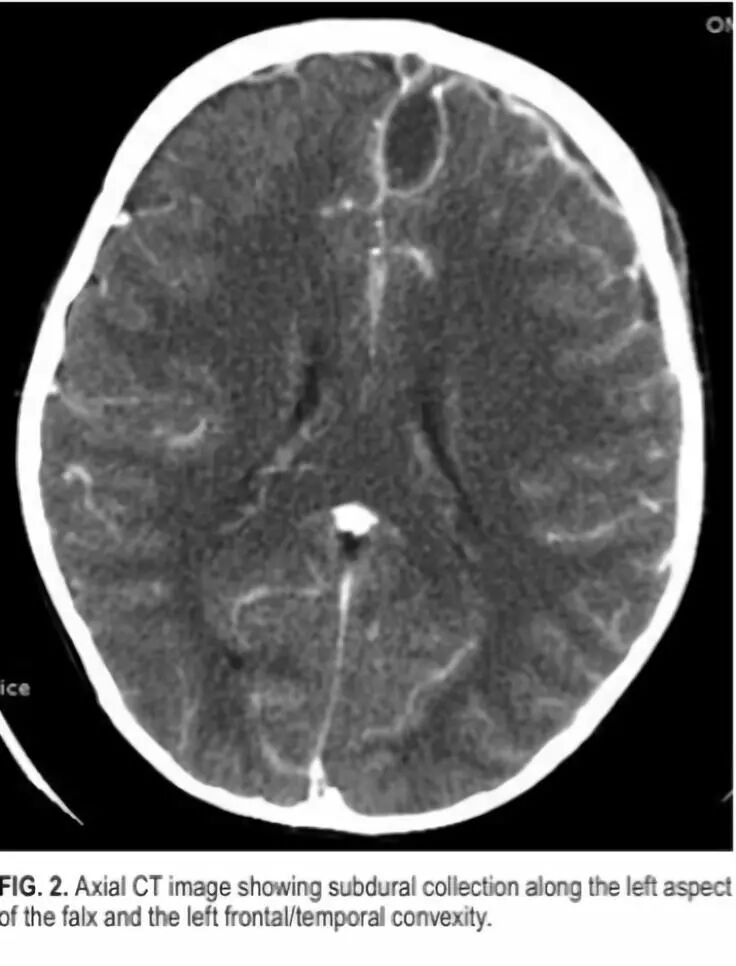

8. 小儿颞叶癫痫静息态连通性的变化

Changes in resting-state connectivity in pediatric temporal lobe epilepsy.

DOI: 10.3171/2018.3.PEDS17701.

功能连通性磁共振成像(FcMRI)是指在无任务、静息状态下分析血氧水平依赖的信号改变的功能磁共振,该技术已被证明在评估癫痫的网络连通性变化方面是有效的。利用18例单侧颞叶癫痫患儿的术前FcMRI资料,作者在患侧和健侧颞叶内行seed-based分析,测量并比较颞叶种子内部和彼此的连通性。研究发现,患侧颞叶局部连通性明显高于健侧颞叶;患侧到健侧颞叶的连通性,显著低于健侧到患侧。患侧颞叶局部连通性的变化低于颞叶间连通性的变化。有或无颞叶内侧硬化症的病人间比较,患侧的连通性改变差异显著。在单侧颞叶癫痫中,应用fcMRI可以观察到患侧颞叶和颞叶间连通性的显著变化。此外,fcMRI可能对顽固性颞叶癫痫患者的术前评估有一定作用。

![]()

颞叶癫痫患者的FcMRI连通性变化